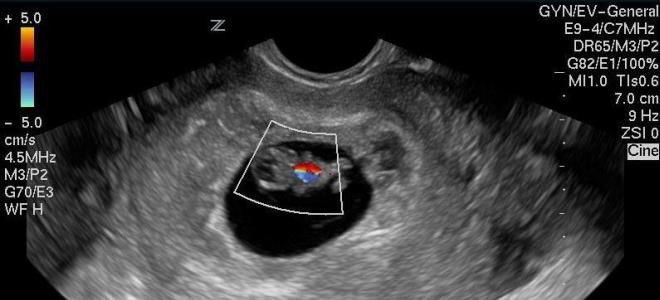

УЗИ на 8 неделе беременности

На восьмой неделе беременности эмбрион еще очень мал, и его внутренние органы и системы находятся на стадии формирования. Учитывая это, медицинские специалисты редко проводят обследования на данном этапе. Если такое исследование все же выполняется, особое внимание уделяется сердцебиению плода, что позволяет оценить состояние его сердечно-сосудистой системы. В норме частота сердечных сокращений у малыша составляет 140–160 ударов в минуту. Важно помнить, что во время процедуры этот показатель может увеличиваться на 10–15 ударов в минуту из-за стресса, который ультразвук вызывает у малыша.